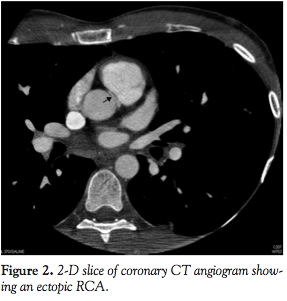

A 25-year-old athletic man had a ventricular fibrillation arrest while running. Electrocardiogram after defibrillation showed ST-segment elevations in leads V1 and V2 and incomplete right bundle branch block, which then normalized. Personal and family history was unremarkable. Echocardiogram showed mild RV dilatation with borderline RV and LV function. Troponin I peaked at 5.55. The patient made a complete recovery. Cardiac MRI demonstrated mild thinning of the RV free wall, without stigmata of arrhythmogenic RV cardiomyopathy. Coronary angiography showed a normal left coronary system with opacification of the RCA on

injection of the left coronary circulation (Figure 1; Video 1, available at www.invasivecardiology.com). A coronary CT angiogram (CCTA) showed an ectopic RCA originating from the left coronary sinus traversing between the pulmonary artery and aorta (Figures 2 and 3).